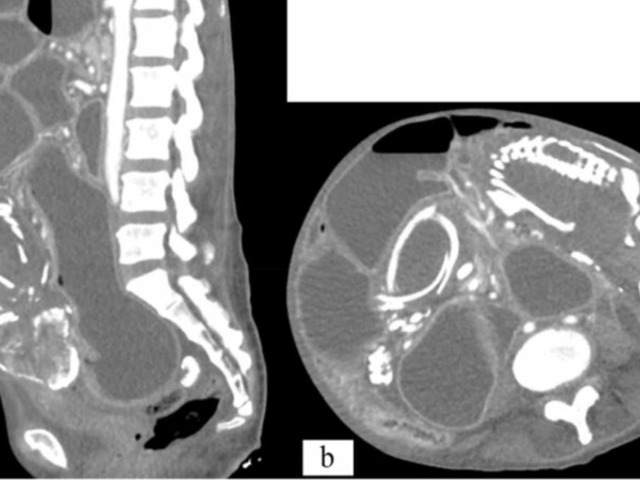

O caso bizarro do "bebê de pedra" foi descrito em um artigo publicado no periódico científico BMC Women's Health. O feto calcificado foi descoberto quando a mulher foi atendida em um hospital com dor e desconforto abdominal. Após exames de raios X, os especialistas identificaram o problema da refugiada: um litopédio, que é um evento médico raro onde o feto morre e se calcifica dentro da barriga da mãe.

O feto estava calcificado no abdômen da gestante há cerca de nove anos. Isso posava uma dificuldade na digestão dos alimentos para a mulher, que sofria, por causa do "bebê de pedra", de obstrução abdominal.

Quando foi atendida nos Estados Unidos e o litopédio foi identificado, os médicos sugeriram uma cirurgia para retirar o "bebê de pedra". A mulher recusou o procedimento por medo da operação cirúrgica, de acordo com informações do UOL. Após o incidente, ela acabou morrendo de desnutrição grave por causa do feto calcificado e das dificuldades que ele apresentava para a digestão dela.